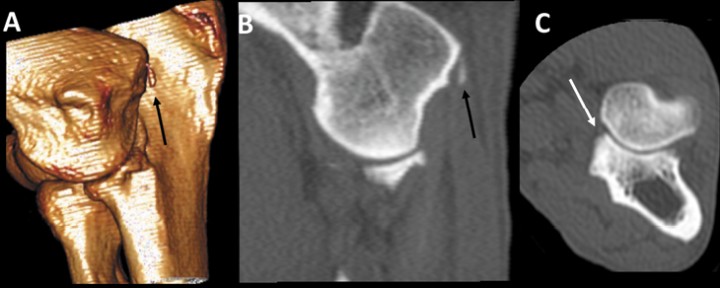

<p>Pastor Alemán hembra de 8 meses, con cojera de dos semanas y dolor en el codo derecho. Imágenes en 3D del codo por la cara medial (<strong>A</strong>) y planos sagital (<strong>B</strong>) y transversal (<strong>C</strong>). La apófisis coronoides medial del cúbito muestra un pequeño fragmento hipoatenuante (flecha blanca) que se confirmó mediante artroscopia. Además, existe un pequeño fragmento hiperatenuante próximo al borde caudodistal del epicóndilo medial del húmero, que no va acompañado de reacción ósea (flechas negras). Esta estructura asociada al tendón flexor es seguramente un fragmento avulsionado, indicativo de una desmopatía crónica.</p>

Pastor Alemán hembra de 8 meses, con cojera de dos semanas y dolor en el codo derecho. Imágenes en 3D del codo por la cara medial (A) y planos sagital (B) y transversal (C). La apófisis coronoides medial del cúbito muestra un pequeño fragmento hipoatenuante (flecha blanca) que se confirmó mediante artroscopia. Además, existe un pequeño fragmento hiperatenuante próximo al borde caudodistal del epicóndilo medial del húmero, que no va acompañado de reacción ósea (flechas negras). Esta estructura asociada al tendón flexor es seguramente un fragmento avulsionado, indicativo de una desmopatía crónica.

Las lesiones del epicóndilo medial son relativamente frecuentes en el perro,[ Gielen I, Villamonte-Chevalier A, Broeckx BJG, van Bree H. D. Different imaging modalities in ED; what is their specific added value? Proc 31st Ann Meet Inter Elbow Working Group. Verona (Italy). 2017: 5-8. , De Bakker E, Samoy Y, Gielen I, van Ryssen B. Medial humeral epicondylar lesions in the canine elbow. Vet Comp Orthop Traumatol 2011; 24: 9-17. [PubMed] ] incluyendo la presencia de pequeñas avulsiones del mismo, y se le ha relacionado con posibles traumatismos en la inserción del tendón flexor digital superficial[ De Bakker E, Samoy Y, Gielen I, van Ryssen B. Medial humeral epicondylar lesions in the canine elbow. Vet Comp Orthop Traumatol 2011; 24: 9-17. [PubMed] ] apareciendo asociado a diversas formas de artrosis de codo. Normalmente existen signos de remodelación del epicóndilo y con frecuencia entesopatías o artrosis asociadas. En el caso reportado por nosotros, la lesión se centraba en el epicóndilo lateral y no se detectaban entesopatías o áreas hipoatenuantes en los músculos asociados que pudieran indicar signos de inflamación asociados. Es verdad que existía una importante remodelación de la porción lateral de la apófisis ancónea, pero dicha remodelación estaba, en menor medida pero también intensa, en la apófisis ancónea del otro codo. Además, existía una clara EACM. No hemos encontrado referencias sobre esta lesión en la bibliografía consultada.